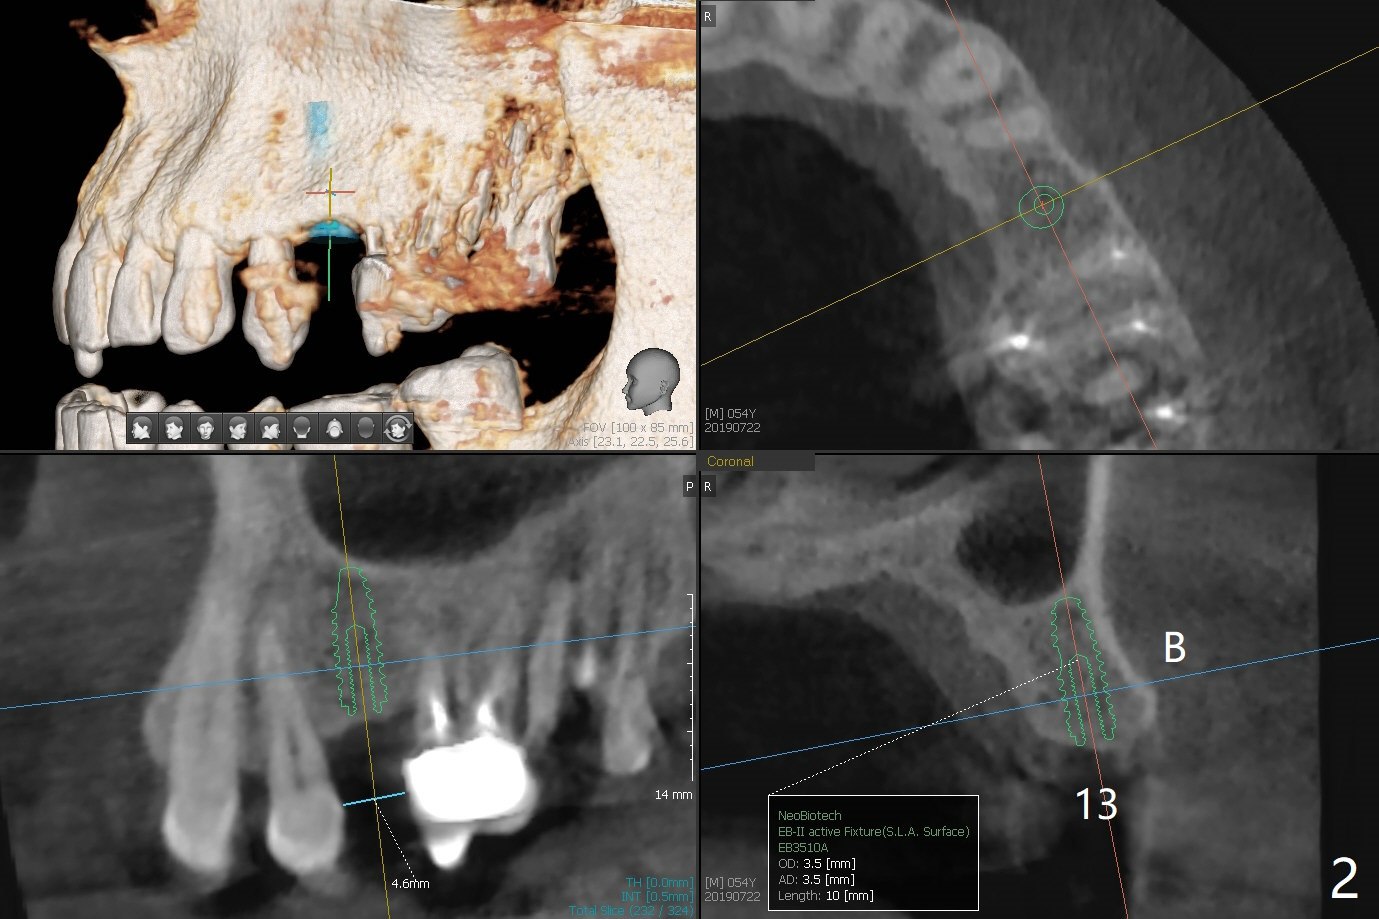

A 54-year-old man has lost a crown at #15 due to root fracture. The latter is associated with bruxism and missing #13. He agrees to have 2 implants and limited ortho to increase the space at #13. In fact the space increases by proximal reduction before CT and impression for guide (Fig.1). The space is enough for a narrow metal sleeve (Fig.4). To prove that abutment screw loosening is most likely related to implant trajectory, IBS implants (with history of easy screw loosening) will be placed with the help of IS guide. PRF will be prepared (x2), one for sinus lift and the other for palatal plate repair. Take photos for palatal fistula.